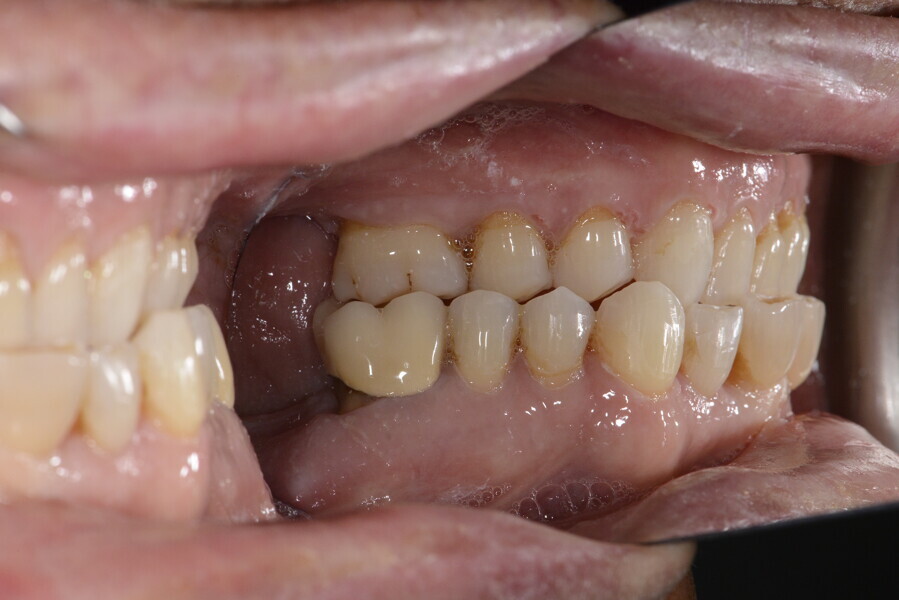

The 58-year-old patient wished to improve his oral aesthetics and function, complaining of mobility of the posterior teeth and wear of the anterior teeth. After data collection, a very complex situation was identified (Figs. 11–13):

1. severe periodontitis with poor prognosis of some teeth;

2. anterior crossbite;

3. severe wear mainly of the anterior teeth and compensatory eruption;38

4. atypical swallowing and lower posture of the tongue at rest;

5. masticatory dysfunction during the mastication test; and

6. no significant signs of temporomandibular disorder.

After the first phase of aligner treatment, we had achieved better inter-arch coherence, better maxillary arch expansion, and some space for improving the anterior tooth proportions restoratively (Fig. 19). We then temporarily restored the anterior teeth directly with composite, closing the spaces, improving the tooth proportions and further increasing the maxillary arch expansion (Fig. 20). We used restorative arch expansion to reduce the orthodontic destabilisation of the teeth to achieve the correct inter-arch coherence and retain the teeth in the cortical bone.38 A refinement aligner phase was undertaken to improve the final alignment of the gingival zenith and to improve the inter-arch coherence (Fig. 21). The periods of the first orthodontic phase and of the refinement were used to augment the mandibular and maxillary bone and to place the implants (Fig. 22). At the end of the orthodontic treatment, the case was finalised with ceramic veneers in the anterior area and temporary restorations on the implants in the posterior area (Figs. 23–26).